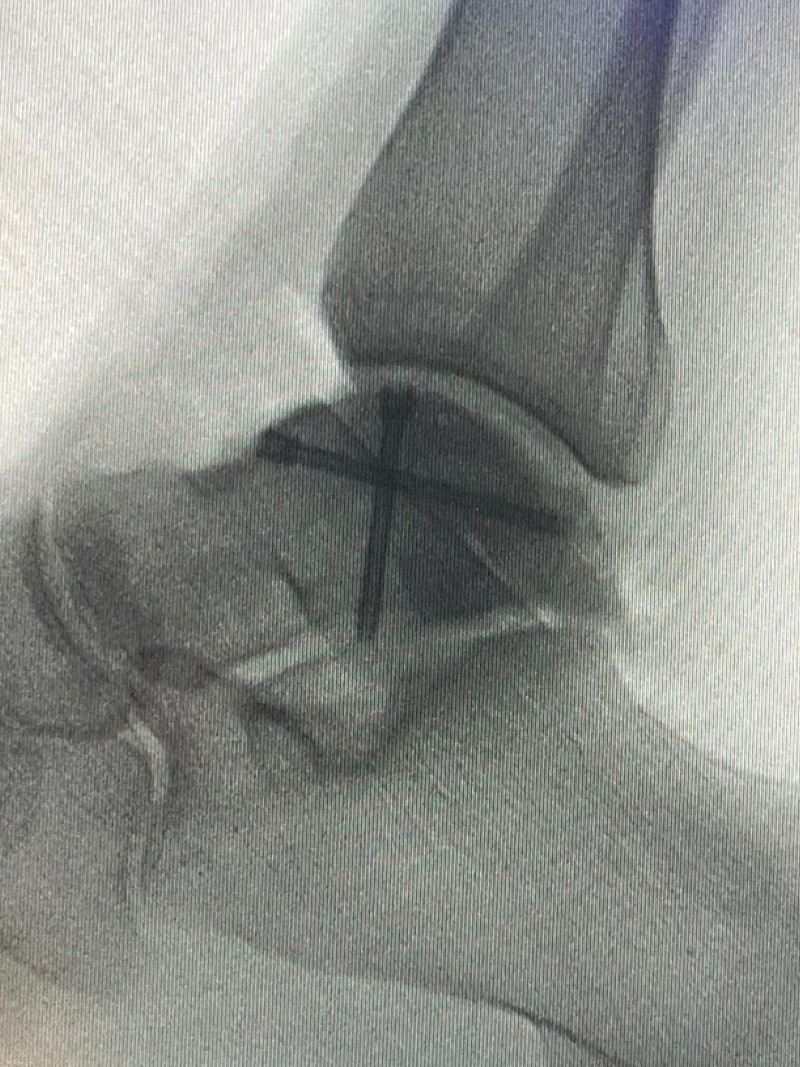

Hastanede yapılan, “Balıkesir’de ilk” nitelikli işlemlerin bir yenisi de Ortopedi ve Travmatoloji Anabilim Dalı Öğretim Üyesi Doç. Dr. Aziz Atik tarafından gerçekleştirildi. Gerçekleştirilen ameliyatla ilgili bilgiler veren Ortopedi ve Travmatoloji Anabilim Dalı Öğretim Üyesi Doç. Dr. Aziz Atik; “Lenf kanseri olan 21 yaşındaki hastamız lenf kanseri tedavisi görerek sağlığına kavuşmuş ancak ilerleyen zamanlarda aldığı tedavilerin yan etkisi olarak ayak bileği kemiğinde çürüme meydana gelmiş. Bize başvuran hastamızın eklem yüzeyi bozulmuş ve hastamız yürümekte zorlanıyor, topallıyordu. Büyük bir lezyonu olan hastamıza büyük lezyonlarda uygulanan en iyi tedavi yöntemi olan ve nadir olarak yapılan bir ameliyatla kadavra donörden kemik ve kıkırdak doku nakli gerçekleştirdik.” ifadelini kullandı. Ülkemizde kemik ve kıkırdak bankası olmadığının altını çizen Doç. Dr. Aziz Atik, yurt dışından bir donör bulmak için çalışmalar yaptıklarını ve yurtdışından kemik bulunduğunda ivedi bir şekilde ameliyatı gerçekleştirdiklerini söyledi. Ameliyatın son derece başarılı geçtiğini belirten Doç. Dr. Aziz Atik, güzel bir eklem düzeyi elde ettiklerini ve ameliyatla genç bir insanın topallamadan, ağrısız yürümesini hedeflendiklerini dile getirdi.